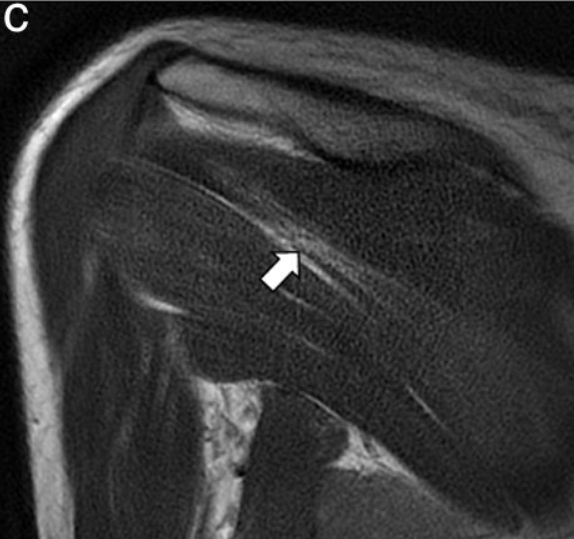

- Resonancia magnética: Cuando se sospeche de otra causa potencial (neoplasia, hernia cervical…) y nos puede mostrar si se realiza el estudio sobre la musculatura afectada. Mostrando patrones de edema difuso en fases iniciales y el aumento de infiltración grasa intramuscular en fase tardía.

Imágenes de este caso clínico